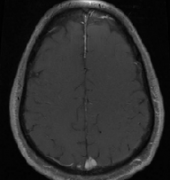

矢狀竇腦膜瘤

INC國際神經(jīng)外科醫(yī)生集團(tuán)為您提供矢狀竇腦膜瘤相關(guān)的前沿治療資訊、成功案例分享、熱點(diǎn)科普知識及國際教授來華信息,想了解更多矢狀竇腦膜瘤資訊請撥打咨詢熱線:400-029-0925

矢狀竇腦膜瘤108例手術(shù)研究報(bào)告

30例完全封閉SSS的腦膜瘤患者完全切除了包裹的部分竇。30例完全封閉SSS的腦膜瘤患者完全切除了包裹的部分竇。30例完全封閉SSS的腦膜瘤患者完全切除了包裹的部分竇。我們進(jìn)行了血管...

矢狀竇旁腦膜瘤好治嗎?順利全切是腦膜瘤預(yù)后關(guān)鍵因素

矢狀竇旁是 腦膜瘤 生長較常見的部位之一,占全部顱內(nèi)腦膜瘤的18-23%。矢狀竇旁腦膜瘤(PMs)與上矢狀竇及引流靜脈的緊密聯(lián)系,使根治性切除難以實(shí)現(xiàn),可能導(dǎo)致神經(jīng)功能的持續(xù)損害,...

矢狀竇旁腦膜瘤的特點(diǎn)和手術(shù)治療

Cushing和Eisenhardt將矢狀竇旁腦膜瘤定義為腫瘤充填矢狀竇旁角,在腫瘤和上矢狀竇間無腦組織。對此,國外也有相關(guān)的研究數(shù)據(jù)為證:辛普森I級切除5年后的復(fù)發(fā)率為35%,II級切除為4%,I...